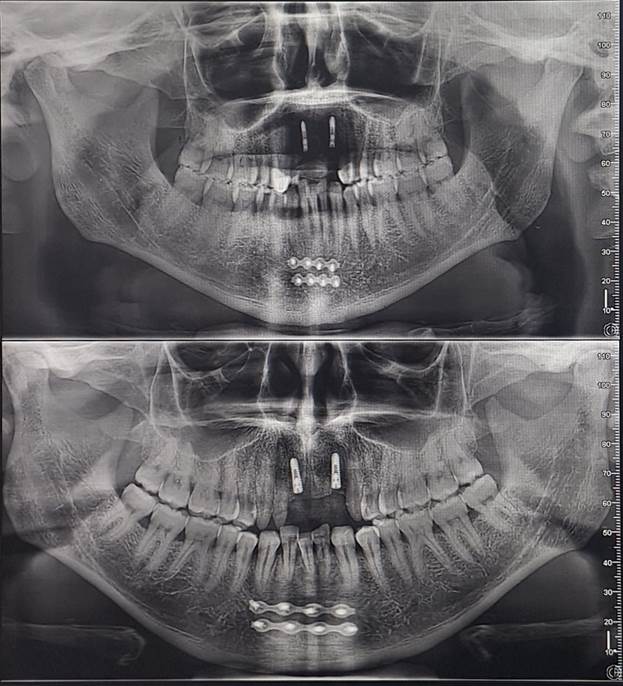

I recently received images of the damage when I got my teeth

repaired and have provided them below.

Initially,

I believed the damage had been repaired correctly. But over time, the injury

had pulled closer together, pushing the bottom middle tooth out of alignment. I

realized I would need to go to the hospital to have it broken and reset. The

thought of enduring that pain again was daunting. However, when I visited

DentaFly, they reassured me that the healing had gone well, and the misaligned

tooth was perfectly fine and fixable. So, I requested a quote for the necessary

treatment.